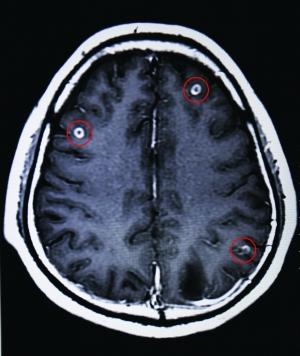

男子脑中寄生19条虫头晕无力视力模糊图

脑囊虫病及其他欢迎来到印度器官博物馆